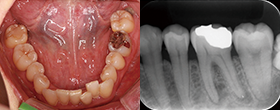

Case2 直線根管

• CC「左下奥違和感」主訴に来院

左下6遠心根に透過像認める

• インレー除去

透過像に一致した部位にサイナストラクト認める

• コンポジットレジンにて隔壁作成

• 作業長確認

最終拡大#30/.04テーパー